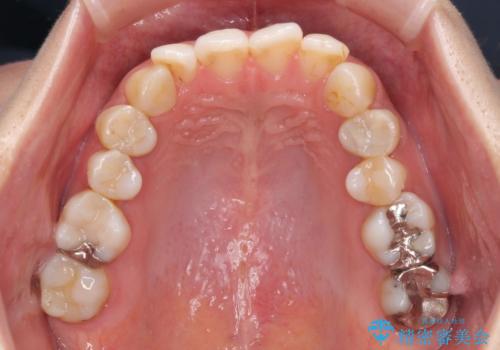

- 失活により変色した歯と不揃いな口元を気にして来院された患者様です。

口元をインビザラインにより歯列を整え、その後に失活している奥歯をオールセラミッククラウンにて補綴治療することとしました。